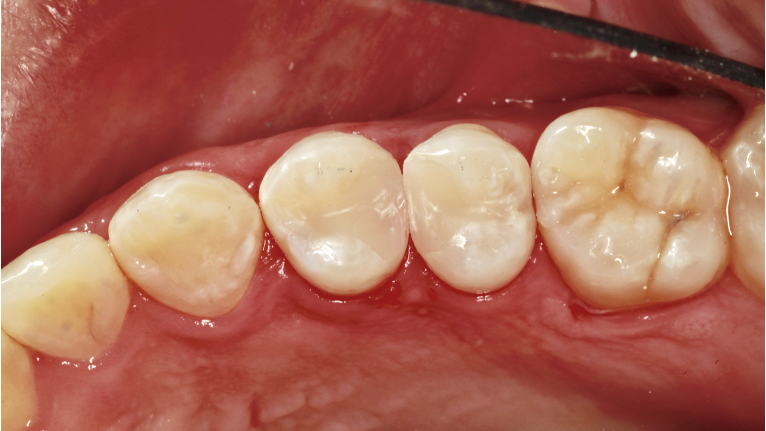

Once the restoration is finished, the rubber dam is removed and the occlusion is checked. Finally, a quick polish is done with a single-step polishing system, the Optragloss. At this point, we have created a great interproximal contact for Lee and restorations that should last very well while we continue to restore his other carious lesions (figure 13).

A post-op bitewing radiograph shows successful restorations for Lee (figure 14).